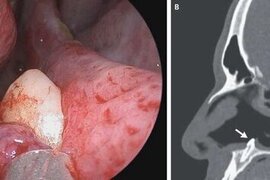

14 yaşlı qızın burnundan diş çıxardılar

Şərqi Sibirdə uşaq xəstəxanasının həkimləri tibdə nadir əməliyyatlardan birini icra edib. xəbər verir ki, 14 yaşlı pasiyentin burnundan diş çıxarılıb. Valideynlərin sözlərinə görə, burnun içində diş uşaq yaşlarından görülüb, amma uşağa heç bir təsiri yox idi. Lakin son aylar qız nəfəsalmada çətinli